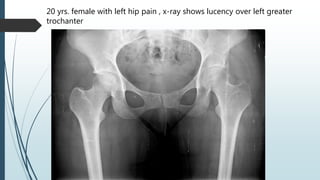

20 yrs. female with left hip pain , x-ray shows lucency over left greater

trochanter